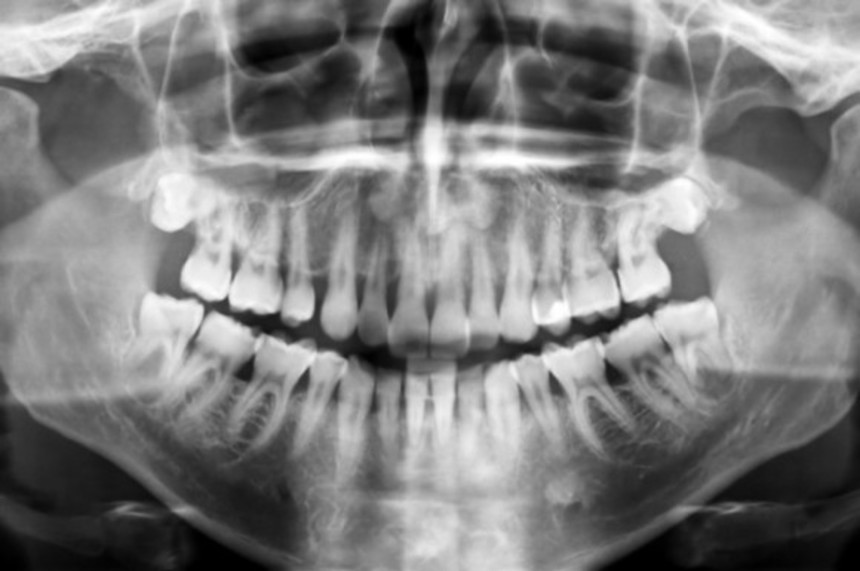

この画像を大きなサイズで見るプラセボ効果は単なる心理上の効果に過ぎないと思われがちだが、肉体的にも反応していることを示唆する強力な証拠がある。2005年、米ミシガン大学の研究者は、14名の健康な男性に対してPET(陽電子放射断層撮影)検査を行った。彼らの顎には痛みを引き起こすための生理食塩水が注射された。そのすぐ後に偽薬が与えられ、やがて効いてくると伝えられた。検査では、偽薬を投与した後にエンドルフィンを放出する脳の領域が活性化したことが確認された。被験者自身も痛みが軽減したと報告している。

2001年に発表された研究では、エンドルフィンを阻害する薬剤を混ぜた偽薬が投与された。果たして、プラセボ効果は起こらなかった。研究は現在も行われている最中だが、この2つの実験からプラセボ効果にはエンドルフィンが関与している可能性が伺える。